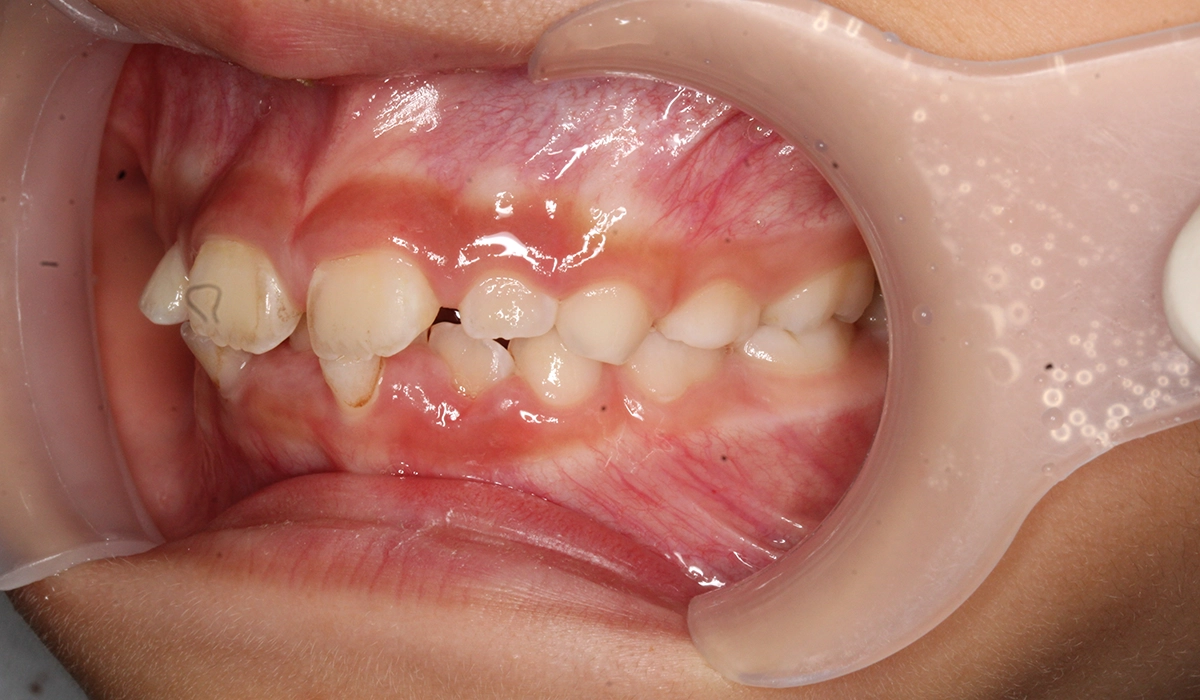

術前:右側

術後:右側